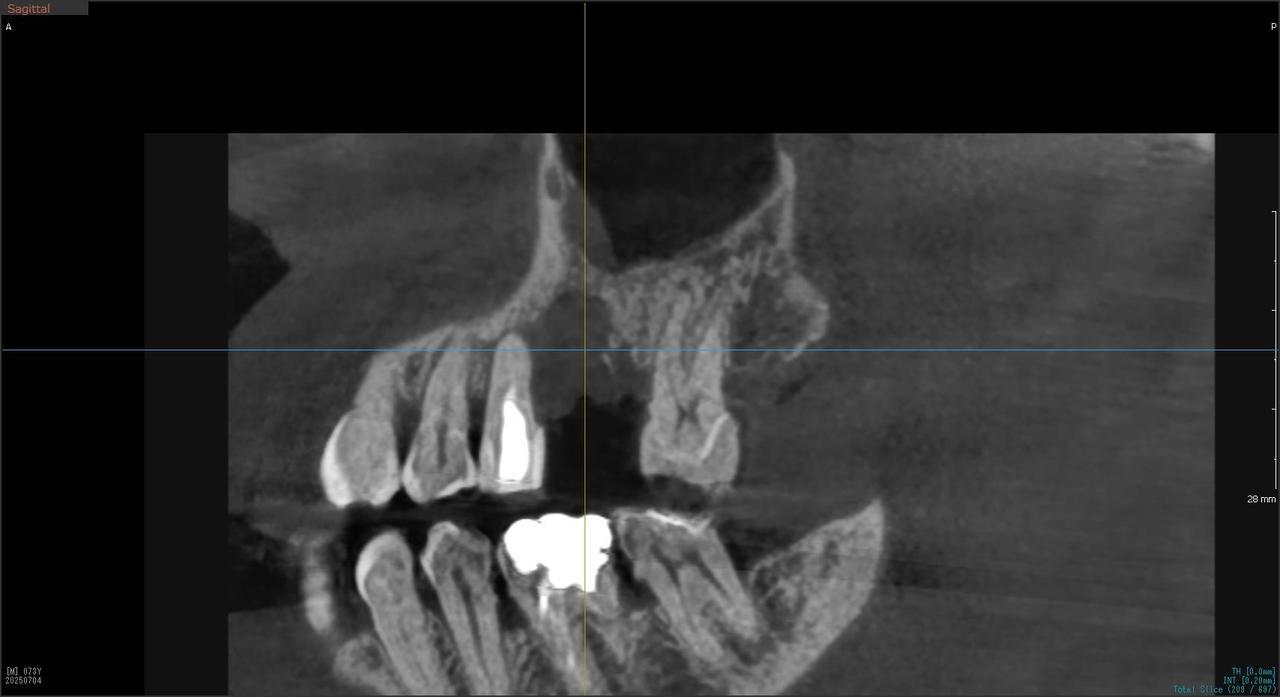

5.左上4番のインプラント抜歯即時埋入、左上6番の上顎既存骨1から2mmのグラフトレスサイナスリフト、左下56の大幅な骨欠損により、下顎神経の損傷を回避するために、ショートインプラントを使用し、左下56にインプラントを埋入し、最終補綴物は、左上456の3ユニットのジルコニアブリッジし、左下56は、ジルコニアの連結冠を装着したケース

Before

枚方市のインプラントの症例

After

M・I 様 女性 70代

症状としては、左下56は、歯周病で欠損したと考えられるが、かなりの骨欠損をともなっていた。左上456に関しては、動揺が大きく、炎症が起き、排膿、および、歯性上顎洞炎を起こしていた。

治療法としては、動揺がひどくなってきて、炎症の症状もあったため、左上56の抜歯を希望。インプラント治療をその後、希望したため、左上4に関しては抜歯即時埋入。左上6に関しては、既存骨1から2mmでインプラント治療が厳しい状態であったが、グラフトレスサイナスリフトを行い、治療期間5か月はかかるということを説明して、インプラント埋入をおこないました。その後、2か月半後、大幅に骨が欠損している下顎56に対して、ショートインプラントを使用して、下顎神経の損傷を避けて、インプラント埋入を終えています。その後2か月後に光学印象で印象を行い、上顎刺億456歯、3ユニットのジルコニアブリッジを装着。下顎左側56に関しては、骨欠損が大きいため、歯冠長がだいぶ長くなるため、ジルコニアの連結冠を装着して治療を終えた。

治療結果は、上顎6に関しては、既存骨が少なく、厳しい治療ではありましたが、5か月で治療を終え、患者様の負担を最小限に抑えるができたと考えます。(従来のサイナスリフトでは、このようなケースでは1年以上、1年程度の治療期間がかかるか、治療が不可能と言われるケースだと考えます。)また、下顎は骨欠損が大きく、下歯槽管のリスクが起きることが考えられますが、ショートインプラントを使用することで安全に治療を行うことができました。

治療の期間・回数:治療期間5か月(上顎456 3ピースブリッジの治療は5か月(上顎既存骨が2mm程度しかなく、骨結合に時間がかかるケースであったために、5か月の治療期間が必要であった。)(左下56に関しては2か月半で治療を終えています。)治療回数は、13回。

治療の価格:1,474,000円(税込)

治療費の内訳:左上46および左下56のインプラント基本料(フィックスチャー及び手術費用、投薬費用、レントゲン費用、インプラント上部費用(アバットメントおよびジルコニアクラウンの費用用)330000円(税込み)×4本分 1320000円(税込)。左上5ジルコニアポンテック費用88000円(税込)。オプション費用、左上4抜歯即時埋入加算(人工骨費用を含む)+グラフトレスサイナスリフト費用 33000円(税込)、左上6グラフトレスサイナスリフト費用 33000円(税込)

治療のリスクや副作用:手術後に、痛みや腫れ、出血、合併症などを引き起こす可能性があります。噛む感覚がご自身の歯と異なる場合があります。見た目がご自身の歯と異なる場合があります。手術後にメインテナンスを継続しないと、インプラントが抜け落ちる可能性があります。